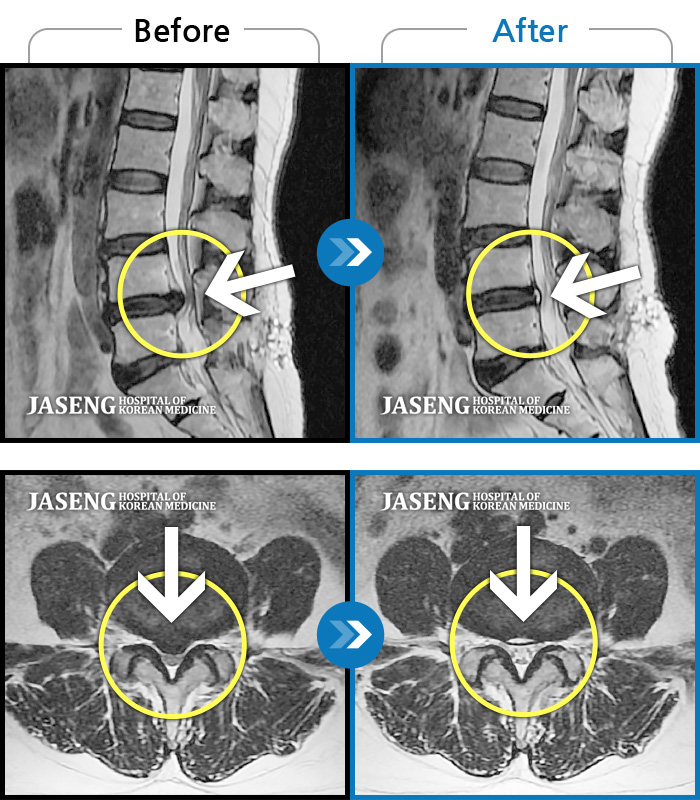

허리디스크

안산 · 김민수 원장

왼쪽 허리에서 다리로 내려가는 심한 통증으로 서 있거나 오래 걷지 못하였습니다.

촬영시기

2022.02.12 ~ 2023.02.17

2023.02.24